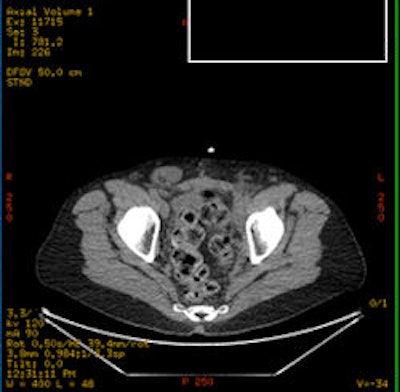

| Above is a traditional PET/CT scan of the pelvis of one individual. The image below is from a choline-PET/CT scan. The top image would appear negative to a radiologist, while the bottom scan is clearly positive for cancer, Karnes said. Images courtesy of Dr. Jeffrey Karnes. |